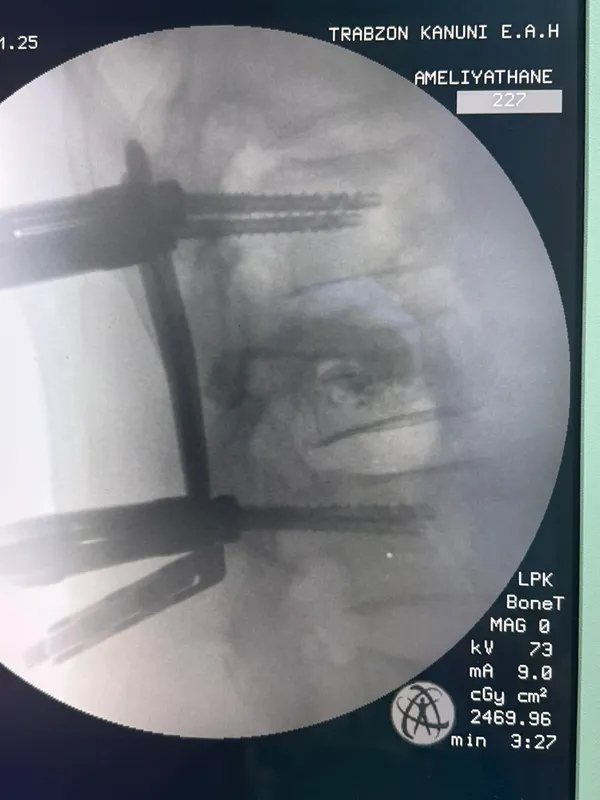

Trabzon'da omurga vidalama ameliyatı geçiren hasta sağlığına kavuştu

TRABZON (AA) - Kanuni Eğitim ve Araştırma Hastanesi'nde omurga vidalama ameliyatı geçiren hasta sağlığına kavuştu.

Hastaneden yapılan açıklamada, ameliyatta kullanılan cerrahi yöntem sayesinde hastaların daha hızlı iyileşme imkanı sağlandığı belirtildi.

Başhekim Prof. Dr. Hasan Rıza Aydın, operasyonun bölge açısından önemli olduğunu belirterek, "Kanuni Eğitim ve Araştırma Hastanesi olarak, hastalarımıza en güncel ve yenilikçi tedavi yöntemlerini sunmaya devam ediyoruz. Bu ameliyat, beyin ve sinir cerrahisi alanında bölgemiz için önemli bir adım olmuştur. Emeği geçen tüm ekibimizi tebrik ediyorum." ifadelerini kullandı.

Ameliyatı gerçekleştiren Beyin ve Sinir Cerrahisi Uzmanı Dr. Gürkan Uzun ise ameliyat ile hastadaki dokuya en az zararın verilerek tedavinin mümkün hale geldiğini vurguladı.

Uzun, kesi bölgesinin çok küçük olması nedeniyle ağrı, enfeksiyon ve iyileşme gibi konularda belirgin bir avantaj sağlandığına işaret ederek, operasyon sonrası hastanın kısa sürede günlük yaşantısına dönebildiğini kaydetti.